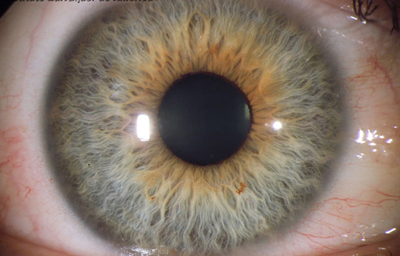

Foto de un Iris humano adulto, con residuos avasculares pigmentados de la membrana pupilar, viniendo del circulo menor. No tiene criptas.

Tomada del archivo fotografico del Dr. CB

Alrededor del 7º mes la vascularización de la porción mesodérmica del Iris, (estroma iridiano) está llegando a su condición definitiva y el circulo vascular menor se reconoce; la túnica vasculosa lentis ya se ha atrofiado en sus porciones posterior y lateral, e inicia atrofia de su porción anterior (membrana pupilar) afectando en primer lugar su zona central; primero en las arcadas finales del centro los vasos se encogen, pierden circulación y quedan formando pequeñas espirales; el ectodermo iridiano con el esfínter ya se ha profundizado, está a nivel de las segundas arcadas vasculares de la membrana pupilar; cuando progresivamente la segunda arcada se atrofia, la membrana queda separada del margen pupilar y toma la apariencia de 2 capas: una anterior (la membrana pupilar) y otra posterior, el margen de la verdadera pupila. Esa grieta o seudoespacio tiene una extensión muy variable; por lo general, solo se ve en el borde de la pupila, pero puede ocurrir que comprometa la capa superficial de vasos periféricamente. Puede ocurrir que el proceso de atrofia no se detenga en la infancia y continue lentamente a lo largo de la vida, hasta que al final toda la hoja vascular anterior se separe del estroma profundo y quede flotando libre en la cámara anterior unida únicamente en la máxima periferia al estroma iridiano (Iridosquisis).

Lo que generalmente se ve, son parches de atrofia localizados periféricamente al margen pupilar, que toman la apariencia de criptas en el estroma.

El modelado final del Iris adulto, tendrá gran cantidad de variaciones dependientes de la cantidad de atrofia de su hoja anterior y de la pigmentación que desarrolle.

El desarrollo del pigmento en el Iris ocurre después del nacimiento y se define después de los 6 meses. Es de anotar que el esculpido del Iris que se aprecia en los adultos con ojos azules o grises, es debido a la visibilidad de las paredes de los vasos; en los iris muy pigmentados el detalle de la estructura queda oculto.